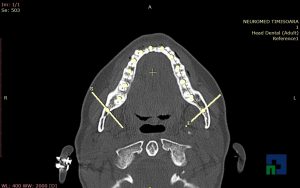

- Diagnosticul fracturilor:

- Unice

- Multiple

- Cu înfundare

- Complexe cranio-sinusale

- Complexe cranio-etmoidale

- Complexe cranio-orbitare

- Complexe cranio-faciale